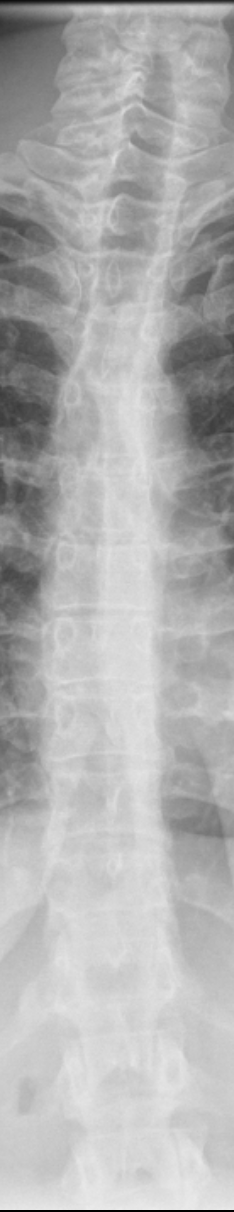

this was from a regular chest X-ray, but I noticed my spine is a little curved, especially my cervical/neck. can this be reversed?